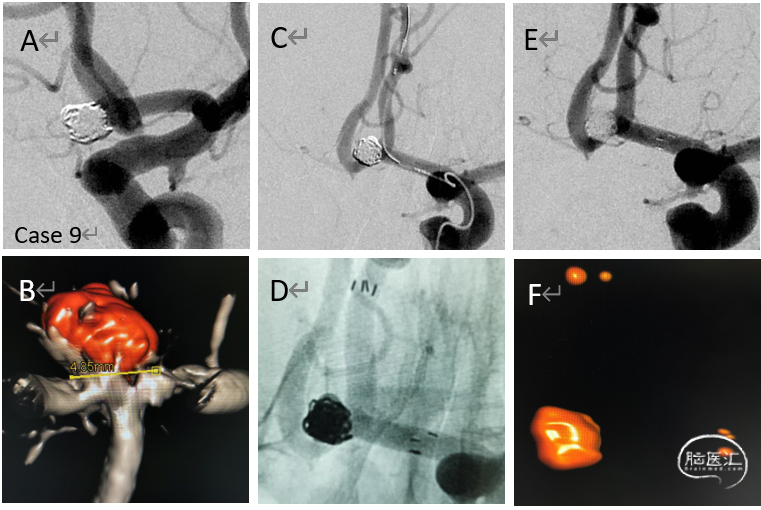

病例9

破裂的前交通动脉瘤急性单纯栓塞

(瘤颈)后二期支架植入

病例10

栓塞的破裂的前交通动脉瘤

(转入)致密栓塞之后二期给予支架植入

病例11

复发的累及PICA的椎动脉夹层动脉瘤

给予追加一枚LVIS,局部推密